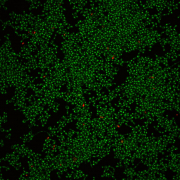

Confocal laser scanning microscopy shows that C. albicans develops biofilms on a plastic surface (left photo), and addition of purpurin suppresses biofilm formation (right photo). Green cells are living and red cells are dead.